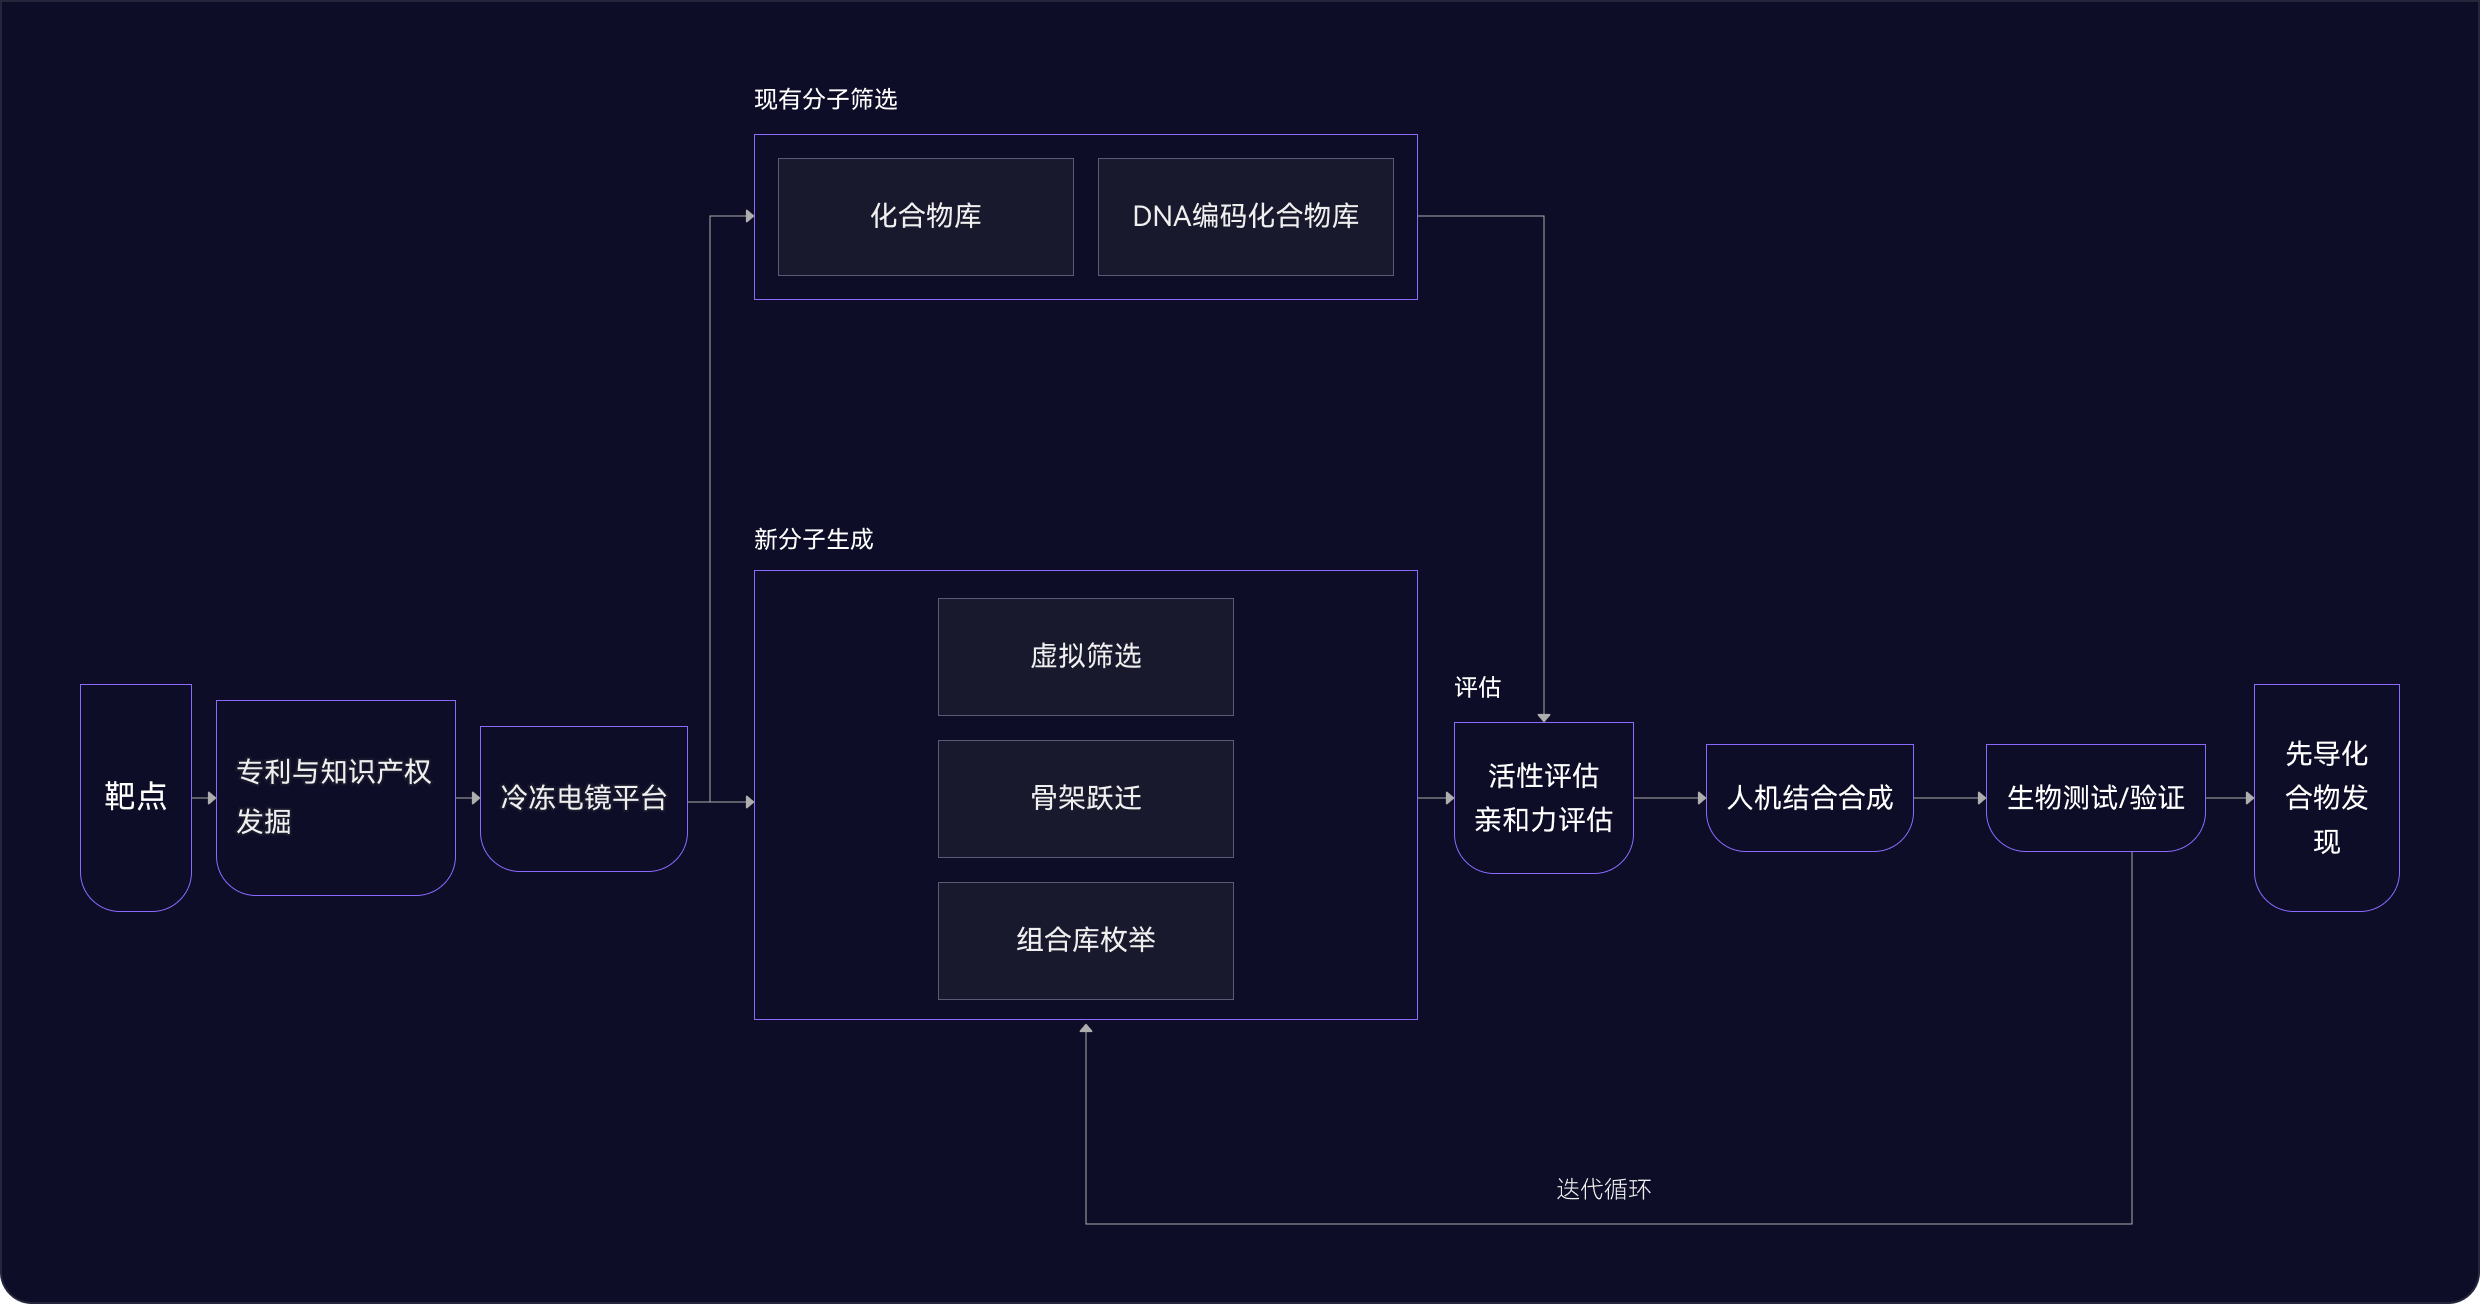

03 藥物發現平臺

ID4Inno 藥物發現平臺

04 苗頭化合物階段

多管齊下

發現最佳苗頭化合物

AI 擴展化學空間

基于AI與物理模型的有機結合,更快、更準確地探索更廣闊的化學空間,開啟您的藥物發現之旅

- 骨架躍遷和組合庫枚舉

- 200萬個分子砌塊,將化學空間擴展到1012化合物庫

- 成功為95%的項目發現苗頭化合物 (60個項目中有57個已完成)

高效藥物篩選

通過全方位的篩選,精準鎖定最具潛力的臨床前候選化合物

- 20多萬種類藥化合物可供購買或內部篩選

- 超過780萬種化合物可通過自動化化學合成

- AI驅動的自動化平臺,實現高效的篩選和數據分析

DNA編碼化合物庫

通過廣泛的多樣性和精準篩選加速發現過程

- 可同時篩選數十億種化合物,增加發現新穎苗頭化合物的機會

- 僅需少量的目標蛋白就可進行測試開發,使早期藥物發現高效且易于實施

05 先導化合物階段

尋找最佳先導化合物

并優化成藥性質

先導化合物評估與優化

通過優化活性、選擇性和類藥性,將苗頭化合物轉化為先導化合物

- 利用生成式AI(XMolGen)進行分子和庫設計,增加骨架新穎性和化合物多樣性

- 通過先進的物理計算(XFEP)進行虛擬篩選,優化活性和類藥性

- 通過專有自動化平臺,實現快速且可靠的中間體和庫合成